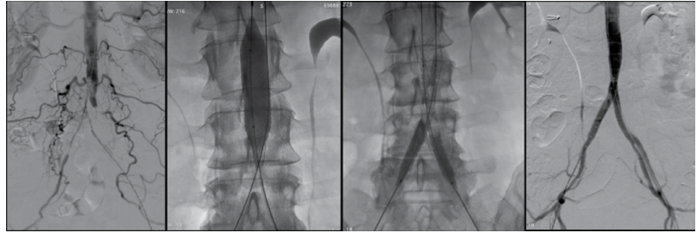

Observe as imagens:

(Arquivo pessoal; imagem usada com autorização)

Assinale a alternativa que corresponde à técnica operatória apresentada nas imag